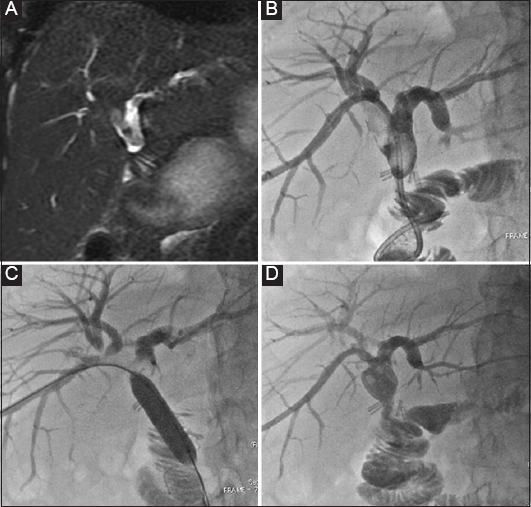

Figure 1 (A) Magnetic resonance cholangiopancreatography (MRCP), confirming the presence of biliary stones in a patient post biliodigestive anastomosis (BDS). Biliary duct dilation indicates the stenosis of the BDS as the underlying factor for stone formation. (B) Percutaneous transhepatic cholangiography and internal external drainage of the biliary system was performed as initial measure to prevent sepsis and to reduce further stone formation. (C) The patient returned 2 weeks later and most of the stones had been reabsorbed. The remainder were pushed via the BDS with a balloon catheter. Dilation of the stenosed BDS followed. (D) an external drainage catheter was left in situ for another 3 days in case hemobilia occurred post dilation. No stones are present in the biliary system